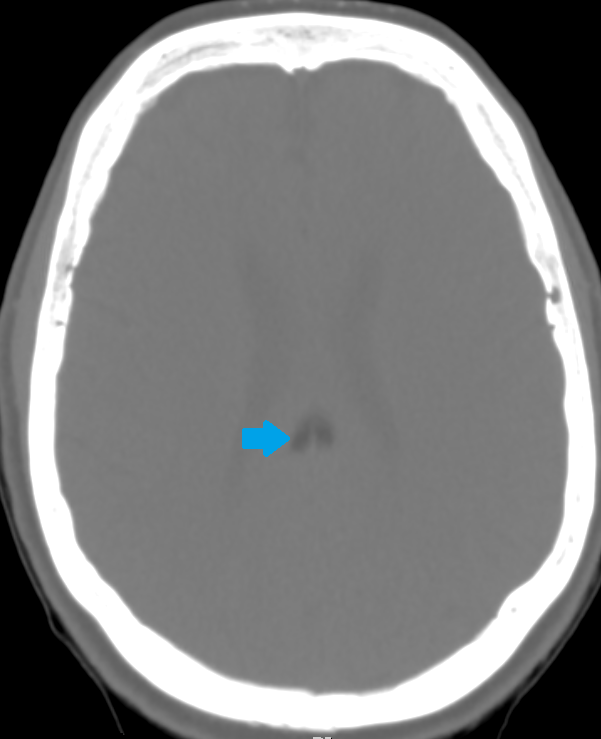

All three images above are non-enhanced head CT’s. First, locate the lesion – it is highlighted by a green arrow in the saggital, and by a blue arrow with bone windowing in the axial imaging. Where is it? What is the density compared to the surrounding brain tissue and CSF? Given the density, what should be in your differential diagnosis?

The most likely structure identified by the green and blue arrows here is:

The answer is B) this is a lipoma. Only fat and air have a density below that of CSF on head CT. Although both lipomas and free air can look similar on normal brain windowing, by adjusting the image settings to bone windowing (middle image with blue arrow above), you will see that the lipoma is no longer totally dark.

Lipomas are relatively common, benign fatty tumors. They tend to be in the midline, just like this one is. They are usually developmental and rarely cause problems later in life – most of the time they are incidental findings like in this case. If large, they can disrupt the development of midline structures like the corpus callosum.